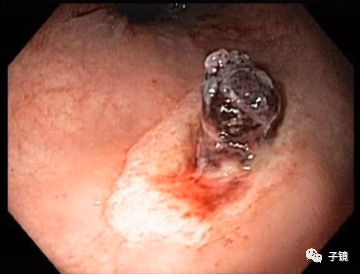

张鸣青教授齿状线的出血主要还是要靠压迫止血,可以在齿状线上方套粘膜,用透明帽压迫一下出血点如果仍有出血,可以打少量硬化剂,或用钛夹夹闭出血灶

唐守江教授遇到齿状线或齿状线下方活动性出血,可以先用钛夹止血,后再套痔上粘膜